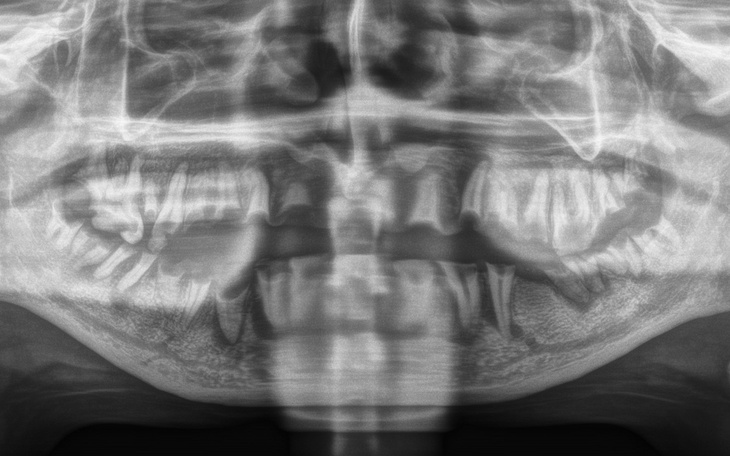

Mam na imię Ewelina mam 27 lat i od dłuższego czasu zmagam się z poważnymi problemami stomatologicznymi, które nie tylko wpływają na moje zdrowie, ale też na codzienne funkcjonowanie, pewność siebie i relacje z innymi ludźmi. Ból, trudności z jedzeniem, wstyd przed uśmiechem – to moja codzienność.

Leczenie, którego potrzebuję, obejmuje kompleksową opiekę stomatologiczną oraz protetykę – odbudowę zębów, które utraciłam. Niestety, koszty są ogromne, a moje możliwości finansowe bardzo ograniczone. Dlatego zwracam się z ogromną prośbą o pomoc – każda złotówka przybliża mnie do życia bez bólu i wstydu.

-usunięcie pozostałości zębów w jamie ustnej

-wykonanie protez : górna i dolna